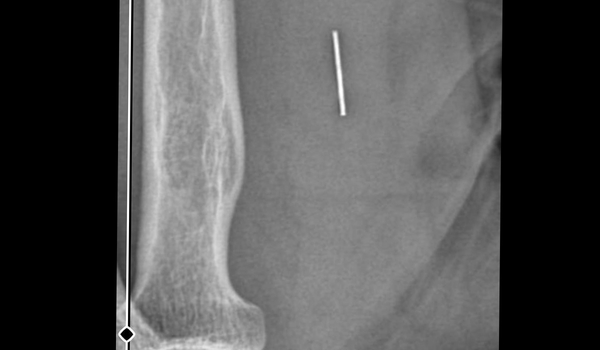

Öte yandan, ameliyatların ardından ağrıları devam eden Güleryüz'ün kolunda metal parça bulunduğu ve bu parçanın parmak bölgesinden dirseğe doğru ilerlediği öne sürüldü. Ayrıca, fabrikada temizlik personeli olarak çalışan Nurettin Güleryüz'ün hastane sürecinde işten çıkarıldığı da öğrenildi.

"KOLUMDA METAL KALDIĞINI ÖĞRENDİK"

İkinci hastanedeki ameliyatların ardından kolunda ağrılar hissettiğini söyleyen Güleryüz, sözlerini şöyle noktaladı:

"Doktorlara bileğime doğru ağrılarım olduğunu sürekli ifade etmeme rağmen beni dinlemediler. Sonradan kolumda metal kaldığını öğrendik. Bunun ihmal olduğunu düşünüyoruz. Çünkü kola metal nasıl girebilir? Ben 9 aydır çalışamıyorum. Kalp rahatsızlığım sebebiyle yüzde 46 engelliyken şu anda yüzde 75 engelli durumuna düştüm. Erken emeklilik dilekçesi verdim ancak henüz sonuç gelmedi. Bu konuda çok mağdurum. Yetkililerin bunu duymasını istiyorum. Savcılığa suç duyurusunda bulunduk. Yaklaşık 9 aydır henüz soruşturma izni gelmedi. Süreci bekliyoruz, henüz dava açılmış değil. Kolumda bırakılan metal ilerliyor. Pazartesi günü bunun için de operasyon geçireceğim. Çıkarılıp çıkarılamayacağı net değil. Elimde titremelerim var, çalışamıyorum ve işveren tarafından işten çıkarıldım. Yetkililerden destek ve konunun incelenmesini talep ediyorum."